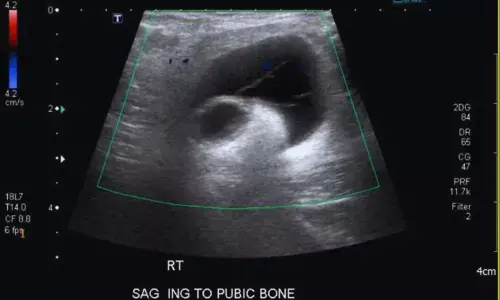

Meshoma: Rare Late Complication of Inguinal Hernia Detectable by Ultrasound — A Case Report

Italy: Meshoma is an uncommon but potentially serious late complication of inguinal hernia repair. Ultrasound serves as a valuable first-line imaging tool, enabling direct visualization of mesh folding and related fistulous tracts, thus aiding timely surgical management. A recent case report published in the Journal of Ultrasound by Giulio Cocco and colleagues highlights the critical role of ultrasound in diagnosing this rare but clinically significant condition.